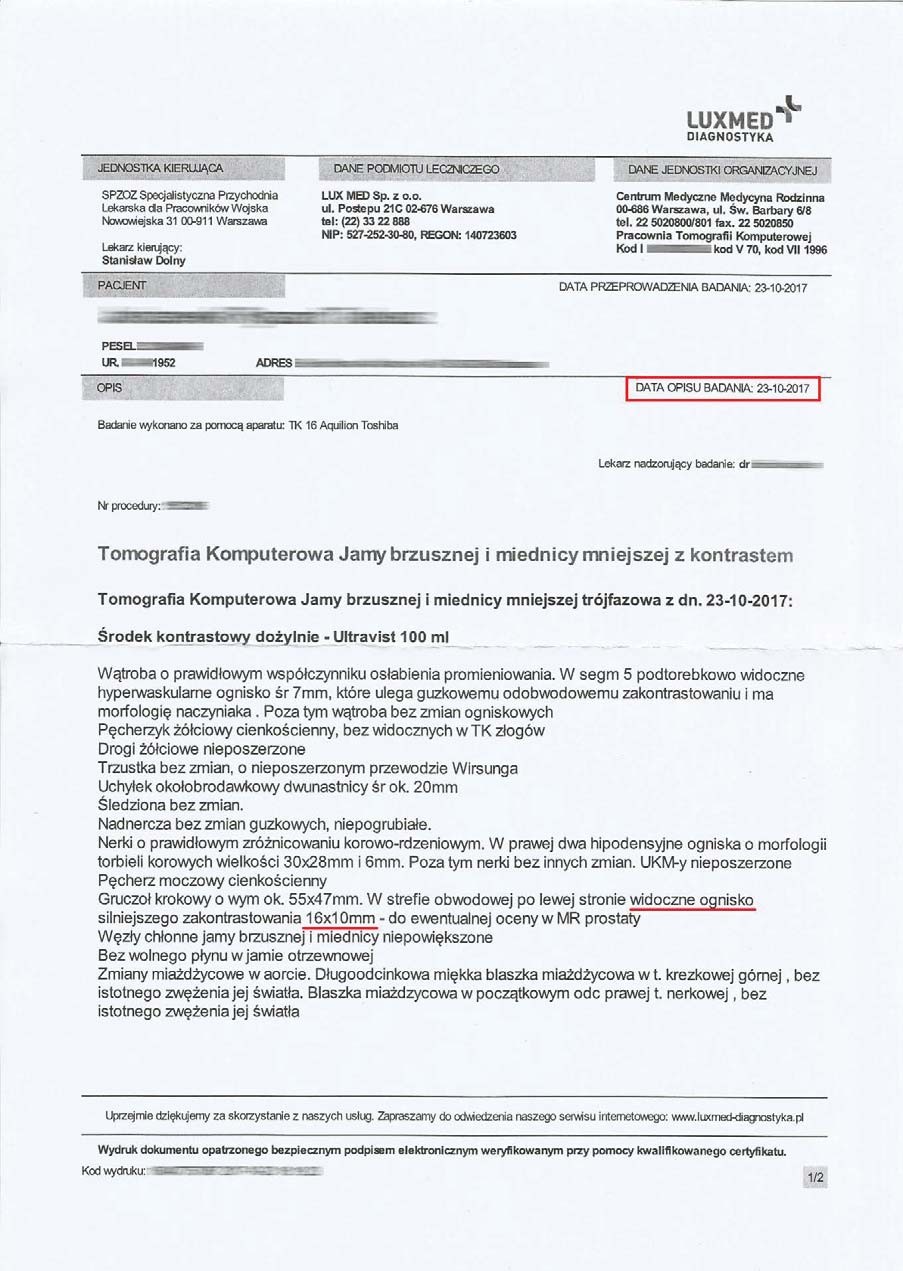

EFEKT PREPARATU NA GUZIE HYPOECHOGENNYM

Mężczyzna lat 66 z guzem hypoechogennym o wymiarach początkowych 16x10mm i wymiarach prostaty 55x47 mm zastosował terapię preparatem, a po 3 miesiącach zaobserwowano pierwsze zmiany w postaci zmniejszenia ogniska do wymiarów 6x7 mm a także zmniejszenie rozmiarów samej prostaty do 50x40 mm.

Badanie po 6 miesiącach stosowania preparatu wykazało brak guza- potwierdzone badaniem obrazowym, dodatkowo prostata zmniejszona do rozmiaru optymalnego (48x61mm), charakterystycznego dla grupy wiekowej. Pełny zanik guza w tak krótkim czasie bez ingerencji chemio i radioterapii wskazuje na głęboką regenerację komórkową. Preparat stymulując mitochondria dostarcza zwiększoną ilość mitochondrialnego ATP, dzięki któremu dochodzi do apoptozy uszkodzonych komórek prostaty. Proces regeneracji komórkowej poprzez stymulację i zabezpieczenie struktury i funkcji mitochondriów wycofuje niekontrolowany podział, co wskazuje na działanie antynowotworowe bez toksyczności.